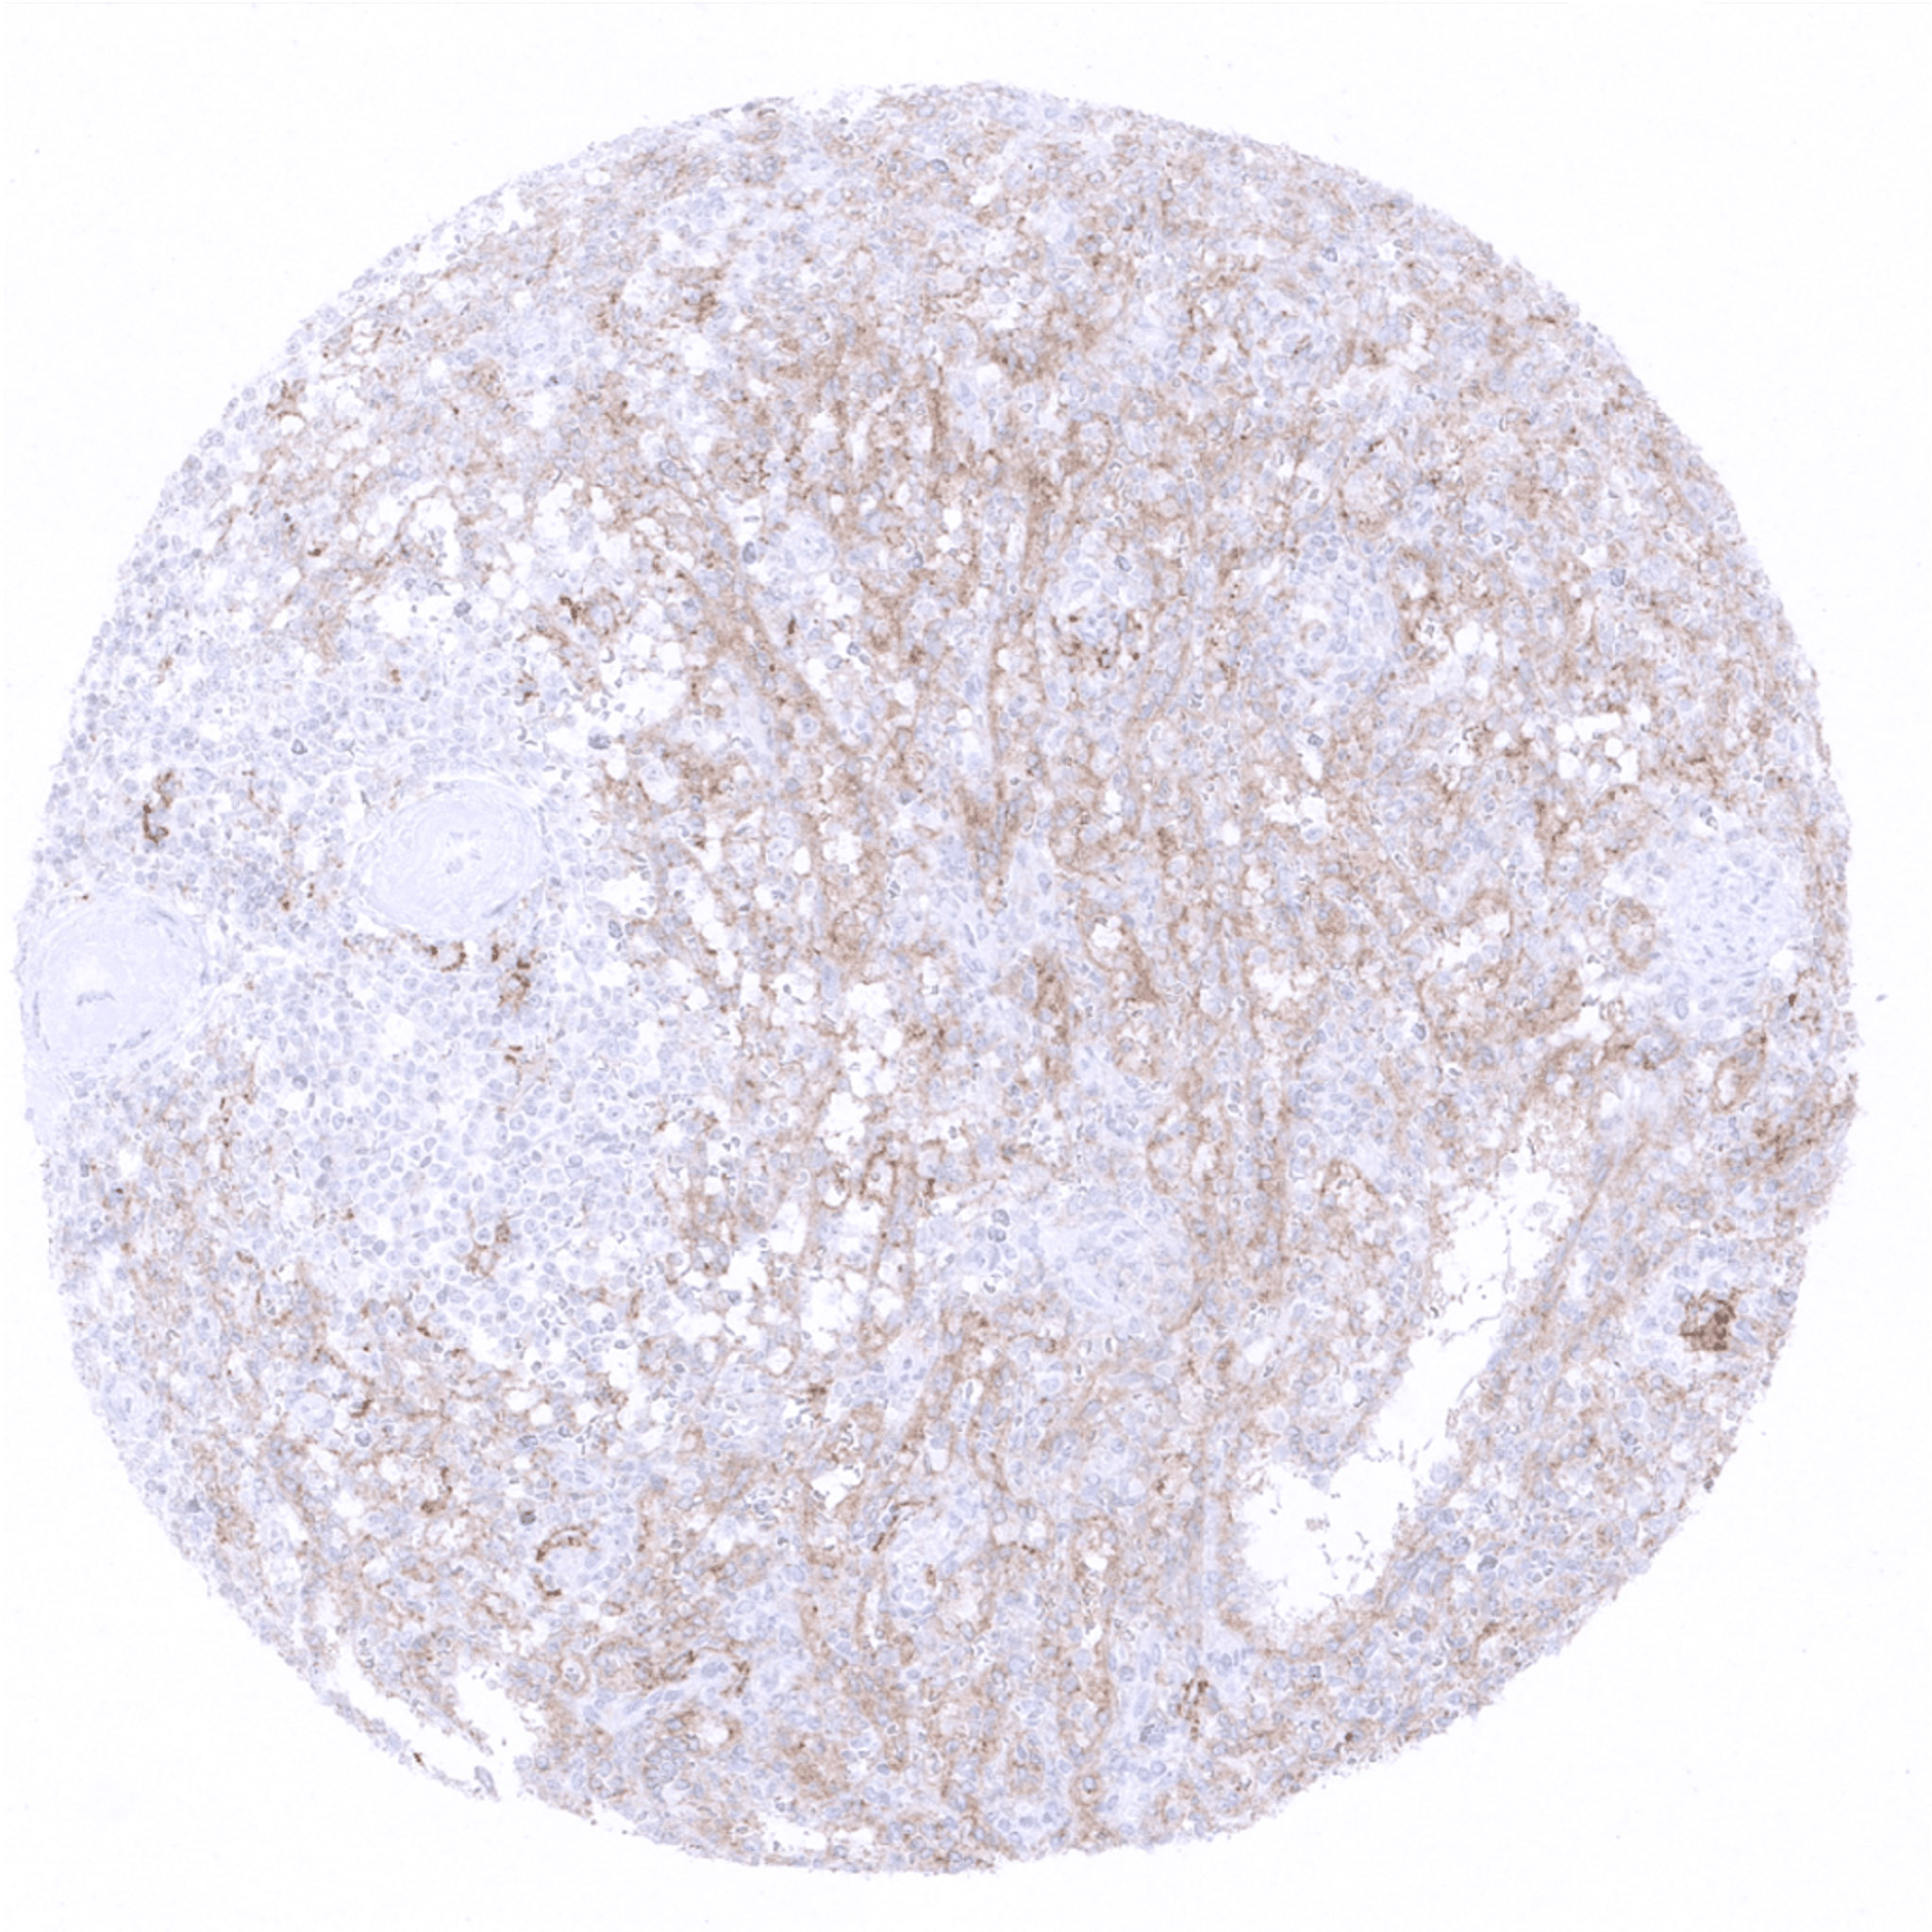

lymph node